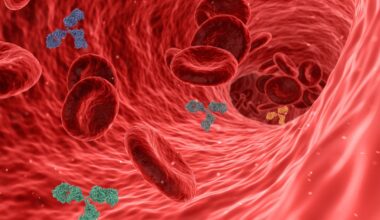

Handball is an intense team sport that not only provides exhilaration but also significantly benefits cardiovascular health. Engaging in regular handball matches can improve heart function, enhance circulation, and promote overall physical fitness. Studies indicate that players experience increased heart rates, which help in strengthening their cardiac muscles. By participating in this dynamic game, individuals can reduce the risks of cardiovascular diseases, such as heart attacks and hypertension. Handball involves running, jumping, and quick lateral movements that elevate aerobic fitness levels. These aerobic exercises are crucial for maintaining a healthy heart and circulation system. Additionally, consistent practice improves endurance and stamina, higher metabolic rates, which in turn assist in weight management. As players practice their skills, they also improve their coordination and agility. This not only results in a more capable athlete but contributes to a healthier lifestyle. Consequently, handball can be seen as both a competitive sport and a form of physical exercise. Emphasizing teamwork and cooperation, handball fosters social connections while enhancing physical health. Ultimately, the positive impact of handball is significant for participant well-being and cardiovascular fitness.

Taking part in handball activities can lead to remarkable improvements in cardiovascular endurance, providing various health benefits. As players consistently train and compete, they experience a significant boost in heart health, which is essential for athletes at any level. Handball players often undergo rigorous training regimens that include interval training, strength drills, and skill practice. Each session challenges their cardiovascular system, fostering adaptations that promote heart efficiency. This sport demands both stamina and explosive power, translating into higher oxygen uptake during intense plays. Studies show that cardiovascular workouts, as performed during handball, stimulate the heart to pump blood more effectively, thus improving overall circulation. This increased circulation helps to maintain healthy blood pressure levels and reduces the risk of heart diseases. Moreover, playing handball encourages individuals to push their physical limits while staying motivated within a team environment. Emotional well-being is enhanced through social interactions and competitive spirit, further supporting cardiovascular health. Staying committed to consistent practice allows players to sustain their endurance and continuously improve their cardiovascular fitness as athletes. Thus, engaging in handball offers a multifaceted approach to achieving better heart health.